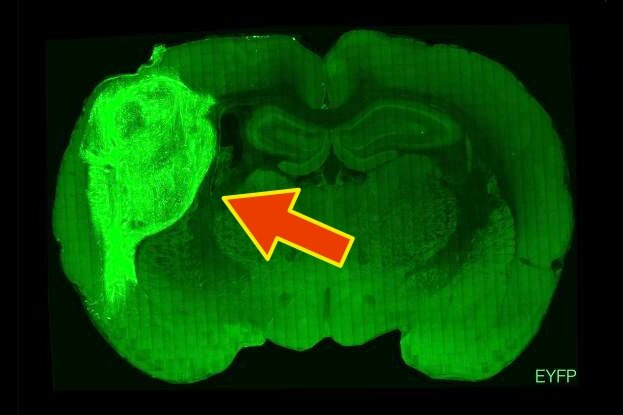

Трехмерные органоиды, созданные из стволовых клеток и напоминающие упрощенную модель коры головного мозга человека, соединены и интегрированы с окружающей тканью в коре каждой крысы, образуя функциональную часть собственного мозга грызуна, проявляющую активность, связанную с сенсорным восприятием.

Это, по словам группы исследователей во главе с нейробиологом Серджиу Пашкой из Стэнфордского университета, преодолевает ограничения органоидов, выращенных на чашках, и дает нам новую платформу для моделирования развития и болезней человеческого мозга в живой системе.